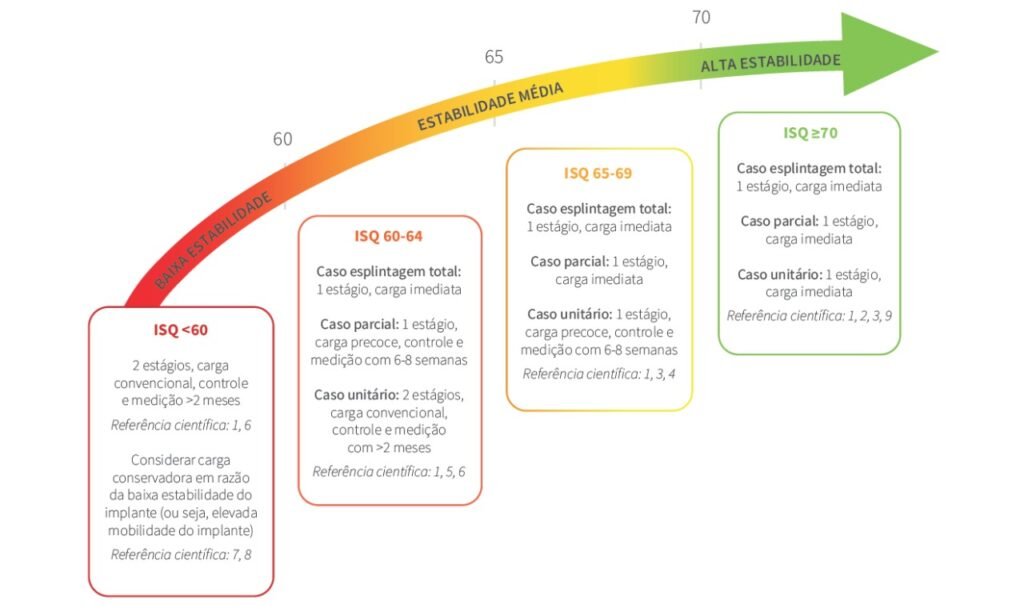

Após muitos estudos clínicos, foi concluído dentro dos parâmetros para o ISQ: de 1 a 25, o implante pode ser perdido, pois o seu índice de estabilidade apresentado pode permitir micro movimentações que influenciam na interface osso implante. De 25 a 100, atingimos uma imobilidade favorável ao implante, permitindo a osseointegração biológica de ocorrer. Mas devemos ter valores acima de ISQ 60, para começar a planejar a carga no implante. Se for uma prótese total esplintada, valores acima de ISQ 60 permitem a carga imediata ou carregamento. Para próteses com múltiplos implantes, devemos ter valores ISQ acima de 65, e para implantes com próteses unitárias, precisamos de um valor ISQ acima de 70. Ver figuras 6 e 7.

– Após a mensuração logo após a instalação do implante, avaliar os valores de ISQ encontrados e decidir a carga de acordo com as recomendações da literatura (ver Fig.7).

– No caso de uma carga tardia, realizar nova medição após a reabertura do implante. Para confirmar a osseointegração biológica do implante o valor ISQ deve estar maior na reabertura do que no dia da instalação do implante. Esta curva ascendente dos valores do ISQ atesta a estabilidade biológica secundária.

– Se o valor for menor do que no dia da instalação do implante, é um sinal de que algo não está correndo biologicamente bem, devendo se reavaliar toda a situação do implante.